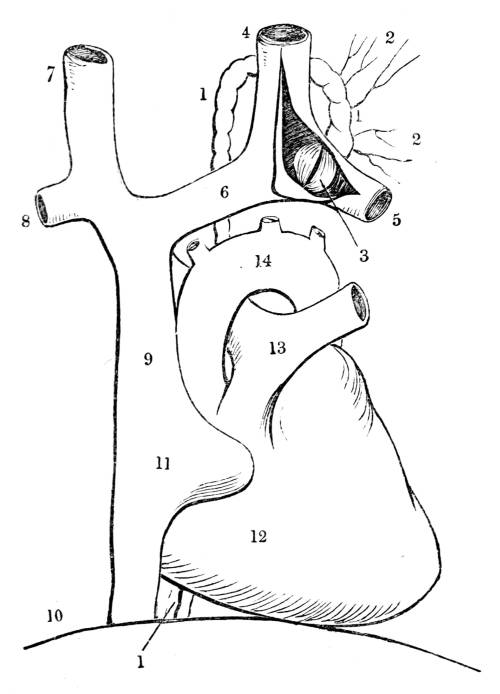

Fig. CXXXIV.—

View of the Respiratory Apparatus in

Man.

1. The Trachea. 2. The right lung. 3. The left lung.

4. Fissures, dividing each lung into, 5. Large portions

termed lobes. 6. Smaller divisions termed lobules. 7.

Pericardium. 8. Heart. 9. Aorta. 10. Diaphragm separating

the cavity of the thorax from that of the abdomen.

357. In man there are two pulmonary bags (fig.

CXXXIV. 2, 3), of nearly equal size, which, together

with the heart, completely fill the large cavity

of the thorax (fig. CXXXIV.), their external surface

being everywhere in immediate contact with

the thoracic walls. One of these bags is placed on

the right side of the body, constituting the right

lung (fig. CXXXIV. 2), and the other on the left,

constituting the left lung (fig. CXXXIV. 3). Each

lung is divided by deep fissures, into large portions

called lobes (figs. CXXXIV. 4, and CXXXV.

6), of which there are three belonging to the

right, and two to the left lung. Each lobe is

subdivided into innumerable smaller parts termed

lobules (figs. CXXXIV. 6, and CXXXV. 6), while the

lobules successively diminish in size until they

terminate in minute vesicles that constitute the

great bulk of the organ (fig. CXXXV. 8).